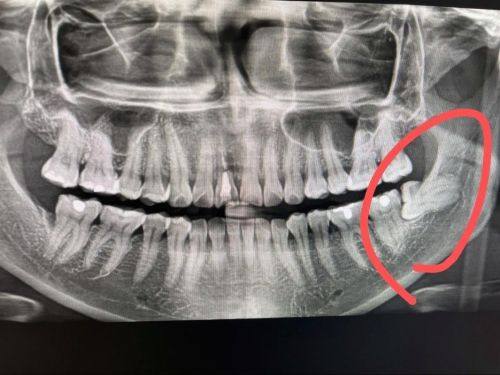

拔牙:包括普通智齿拔除、复杂阻生智齿拔除等,术前精细评估,保护拔牙过程安心舒适